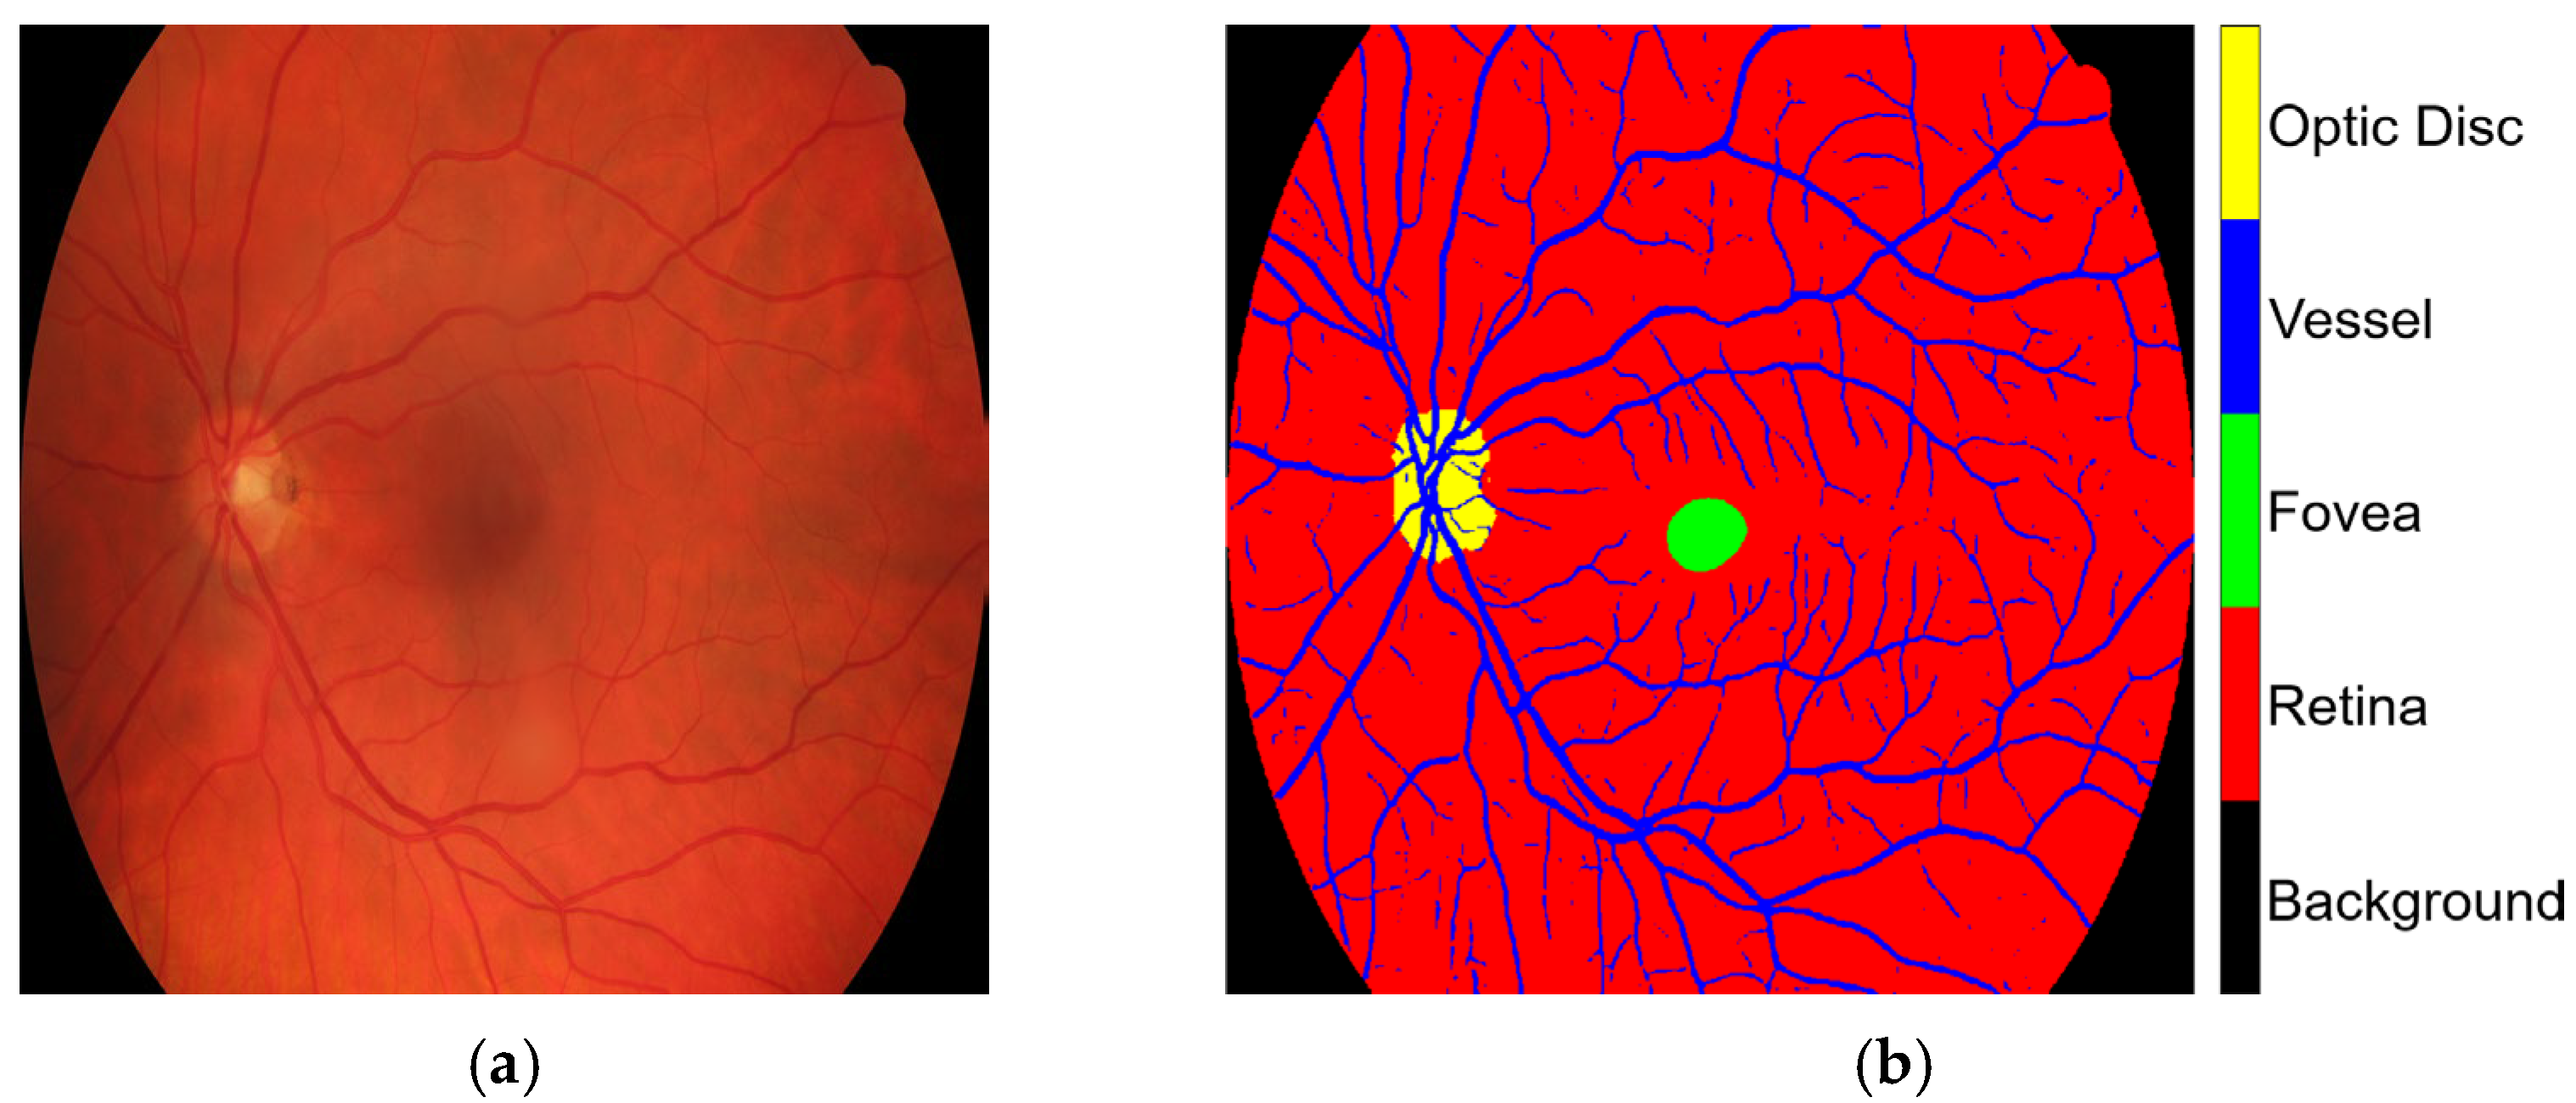

The HRF, DRIVE, and CHASE_DB1 datasets facilitated the examination of label inaccuracies within the CLA framework. The ground truths were first modified by incorporating three additional classes, retina, optic disc, and fovea, as shown in Figure 1. The revised annotations were conducted under the guidance of seasoned ophthalmologists who delivered precise delineations to guarantee accuracy in the segmentation methodology. When these three classes were overlaid, they became major anatomic structures in the retinal images. Blood vessels in the STARE database were manually annotated by two experts, Adam Hoover (AH) and Valentina Kouznetsova (VK), as referenced in [10]. The annotated data are publicly available at https://cecas.clemson.edu/~ahoover/stare/probing/index.html (accessed on 2 July 2025). These annotations are used as reference labels to evaluate label rectification within the PBNR framework.

Figure 1. Example from the HRF dataset: (a) original retinal image, Image1024-02_g; and (b) corresponding ground truth annotation.